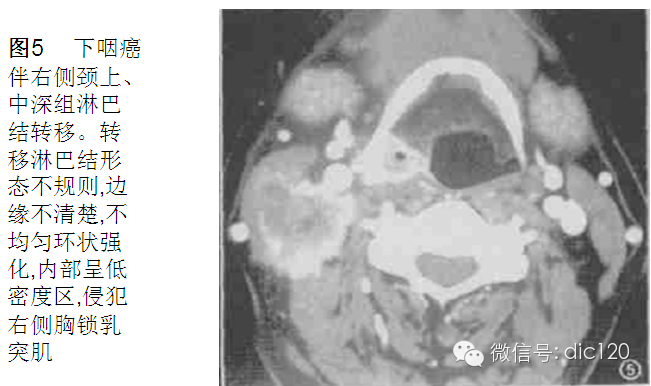

转移淋巴结发生部位和原发肿瘤的淋巴引流区域相关,口腔癌淋巴结转移主要发生于Ⅰ、Ⅱ、Ⅲ区,而口咽癌、下咽癌和喉癌主要发生Ⅱ、Ⅲ区.鼻咽癌转移淋巴结多为双侧发生,除常见于Ⅱ、Ⅲ、Ⅳ区外,咽后组、颈后三角区为鼻咽癌淋巴结转移的特征性部位,这与其他部位原发肿瘤有极显著性差异 。故咽后组淋巴结肿大时,应首先考虑鼻咽癌可能,若同时伴有颈后三角区淋巴结肿大,则诊断准确性更高,但需与淋巴瘤鉴别。

转移淋巴结形态及边缘

表现为形态规则且边缘清楚与形态不规则且边缘不清楚者,其原发肿瘤之间存在极显著性差异 。鼻咽癌及甲状腺癌中,形态规则且边缘清楚者分别为 88 % 和 86 % 。口咽癌,喉癌及下咽癌中形态不规则且边缘不清者分别为59 % 和68 % , 且外侵明显。这与口咽癌、下咽癌及喉癌分化差, 恶性程度高有关。